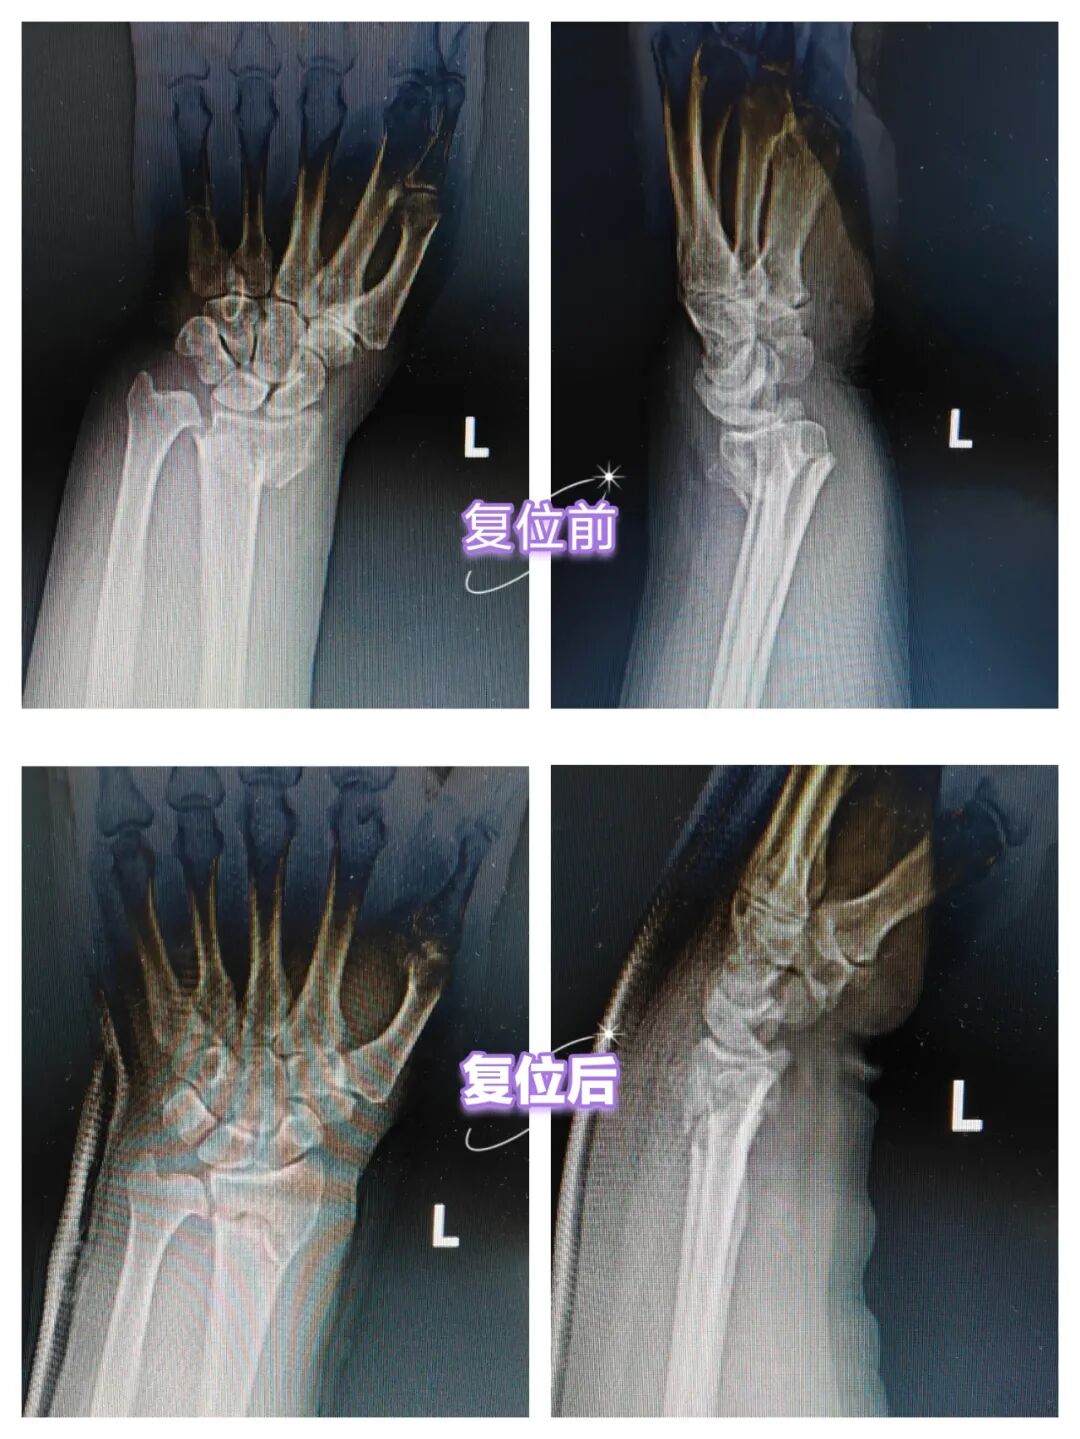

李女士如往常一般,早早起床出门给家里置办中午的饭菜,但刚刚出门没多久就在“冰上雪”摔了一跤,撑在地面的左手传来一阵疼痛,在家属的陪同下,来到长治二院急诊医学科就诊,张晓波医生查体腕部呈“餐叉样”畸形,X线显示为桡骨远端骨折。张医生和家属沟通了病情与治疗方案之后,在局部麻醉下对患者进行了骨折手法复位。